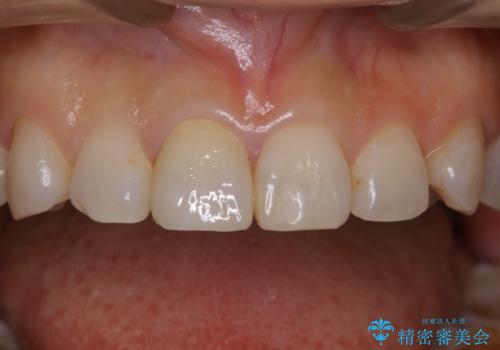

前歯の変色 オールセラミッククラウン

担当医 河口智英